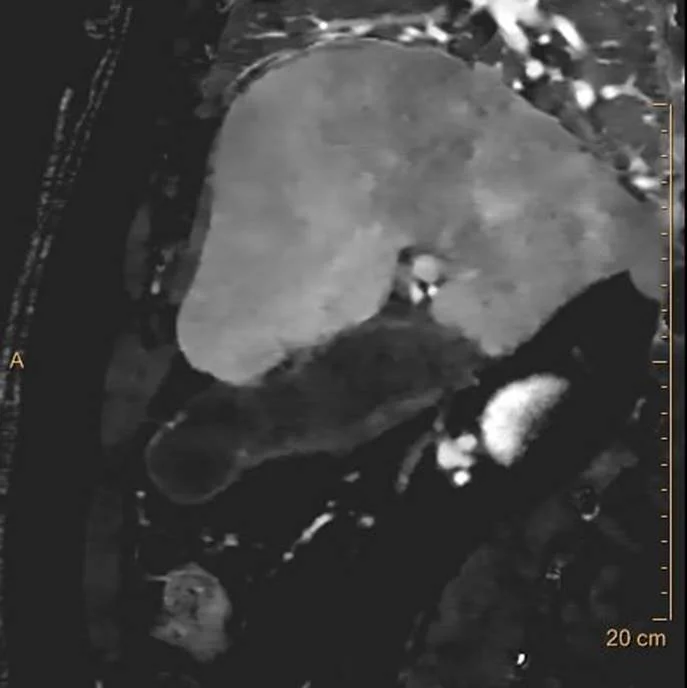

Conventional CT, sagittal image. Thick gallbladder wall with adjacent fat stranding, consistent with acute cholecystitis.